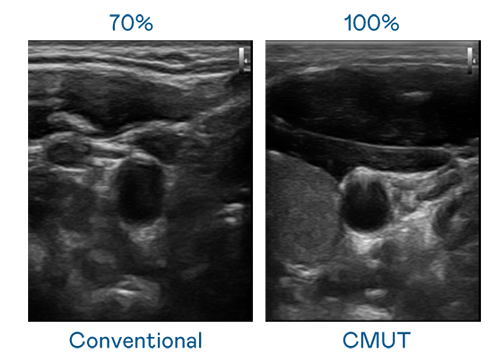

CMUT 技术是一种用电容式微机电元件来产生超音波讯号的技术。与传统 PZT 压电式技术相比,CMUT 频宽增加 30%,更宽频的超音波讯号让影像解析度大幅提升,是实现高影像品质医疗超音波扫描、促进精准医疗发展的关键技术。

大频宽带来超清晰影像

超音波影像的解析度高低,首先取决于探头能发出的讯号频宽。OG视讯 CMUT 可提供高清晰的超音波讯号,提供高频宽、高灵敏度、影像纹理细节更高的超音波影像,协助医护人员缩短影像判读时间及利用精准的医疗影像进行诊断。